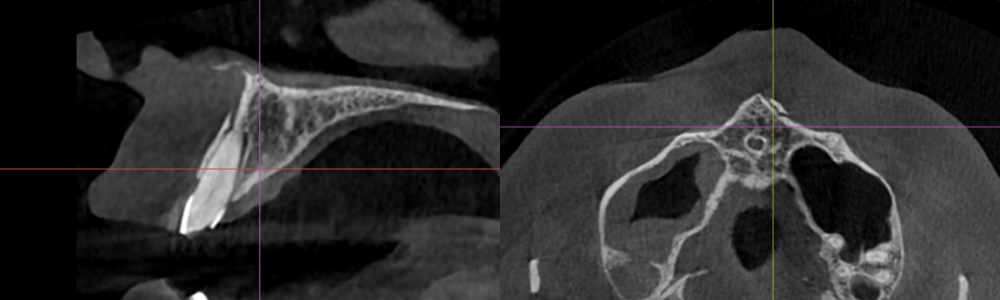

치아 외상으로 인해

크게 이가 부러졌다면,

방사선 촬영을 통해

이를 잡아주는 치조골에는

문제가 없는지 확인을 해야 되는데요.

2025.02.12

촬영본을 확인해 보았을 때

협측 치조골의 골절이 있는 것으로 보아

이가 흔들릴 것으로 판단되며,

치아 고정술이 필요해 보입니다.